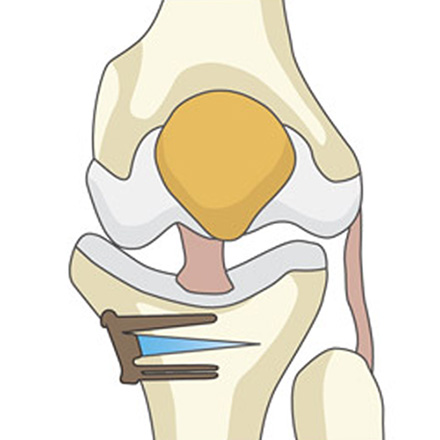

01

정강이뼈(경골) 윗부분을 약 3~5cm 절개한 뒤, 정강이뼈에 금을 냅니다.